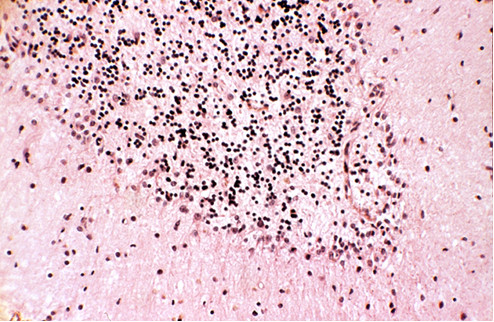

Zwyrodnienie ziarnisto-wodniczkowe (Simchowicza) neuronów piramidowych hipokampa obserwujemy najczęściej w następujących zespołach chorobowych:

Choroba Picka, w której niezbędnym do rozpoznania elementem stwierdzanym w badaniu mikroskopowym są srebrochłonne wtręty neuronalne tzw. ciała (kule) Picka występujące w neuronach korowych i w neuronach zakrętu zębatego hipokampa, należy do następującej choroby przebiegającej z otępieniem:

W przebiegu tej choroby występuje zespół hipertoniczno-hipokinetyczny a pierwszymi objawami ocznymi jest niemożność patrzenia w dół. Zaburzenia poznawcze mają postać otępienia podkorowego. W badaniu neuropatologicznym makroskopowym w mózgowiu opisywany jest głównie zanik gałki bladej i jądra niskowzgórzowego, nakrywki pnia mostu odbarwienie istoty czarnej i gałki bladej. W badaniu mikroskopowym widoczne jest w neuronach zwyrodnienie neuro-włókienkowe, nici neuropilowe, glejoza, ubytki neuronalne i demielinizacja głównie konarów górnych móżdżku oraz gromadzenie białka tau przede wszystkim w cytoplazmie astrocytów. Opis dotyczy następującej jednostki chorobowej:

Zespoły paranowotworowe wywołujące zaburzenia czynnościowe ośrodkowego układu nerwowego, które mogą wystąpić u chorych z ogólnoustrojowym nowotworem bez ognisk w OUN, charakteryzują się zmianami neuropatologicznymi przede wszystkim w następującej strukturze: